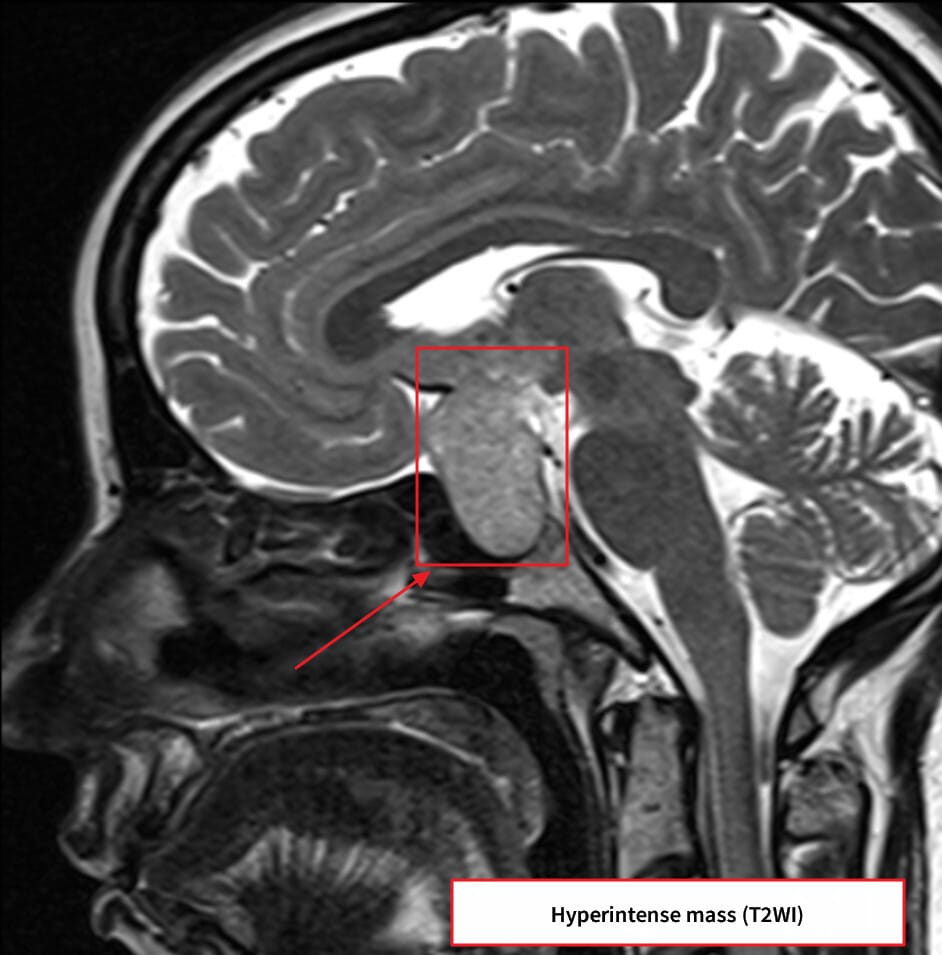

| 거대 선종(>10mm)에서 조영증강된 비균질 종괴로 나타나며, 주변 구조 압박 여부를 확인합니다. |

거대 선종에서 시신경 압박 및 해면정맥굴 침범 여부가 중요합니다.

| ✅ 조영증강 MRI에서 불균질 조영 |

| 종양은 T1 조영에서 주변보다 낮은 조영도를 보이며 비균질한 양상입니다. |

| ✅ 시신경 교차 압박 가능성 |

| 상방으로 확장된 종양이 시신경을 눌러 시야장애를 유발합니다. |